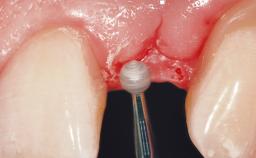

In 2004, a 36-year-old male patient, a non-smoker, presented due to acute pain in the premolar region of the upper left jaw. An orthopantomograph revealed that tooth 24 had been endodontically treated. It also became evident that, during root-canal filling,endodontic filling material had been pushed beyond the apex. This material was located very close to the maxillary sinus floor. Due to this finding in combination with the severe pain and a possible root fracture, tooth 24 was extracted. The esthetic expectations of the patient were not too high and his individual esthetic risk profile summed up to a medium risk profile.